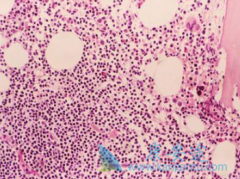

慢性粒细胞白血病是四种最常见的白血病之一,占白血病病例中大约15%。如果不治疗,慢粒将在3~5年的时间里,从初期(慢性期)经过一个过渡期(加速期)发展到急变期,从而迅速致命。 达希纳 (Tasigna)是在格列卫(伊马替尼)的基础上进行改进而研制出的格列卫 ...